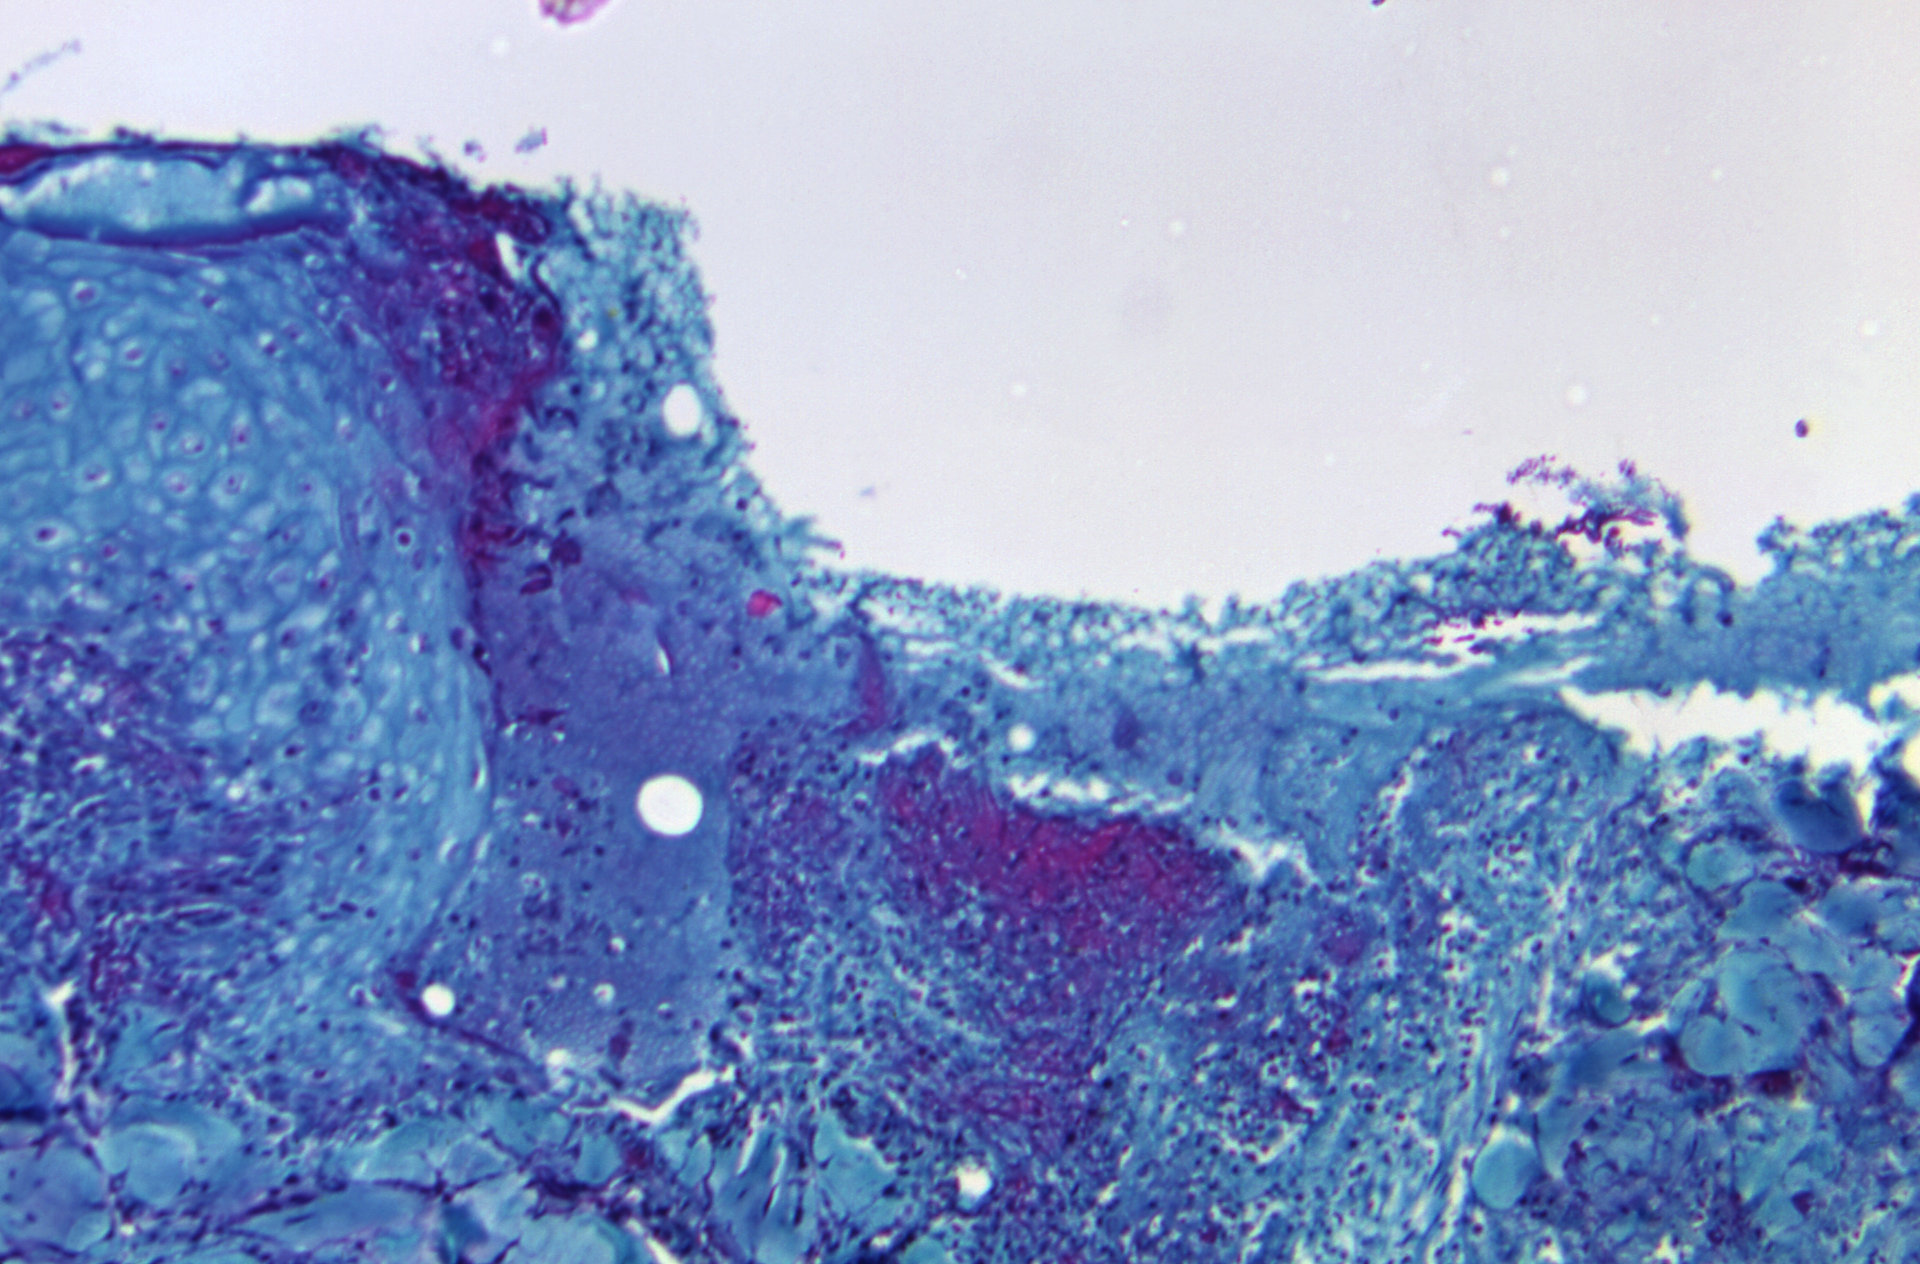

Monkeypox is a rare but potentially serious viral illness that typically begins with flu-like illness and swelling of the lymph nodes and progresses to a widespread rash on the face and body. Monkeypox re-emerged in Nigeria in 2017 after more than 40 years with no reported cases. Since 2017, 218 cases have been confirmed in Nigeria and eight cases have been reported in international travelers from Nigeria, including a case in Texas in July 2021 and the current case.